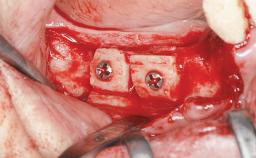

| Bone Augmentation | Staged|Vertical |

| Augmentation Materials | Autogenous chips|Membrane |